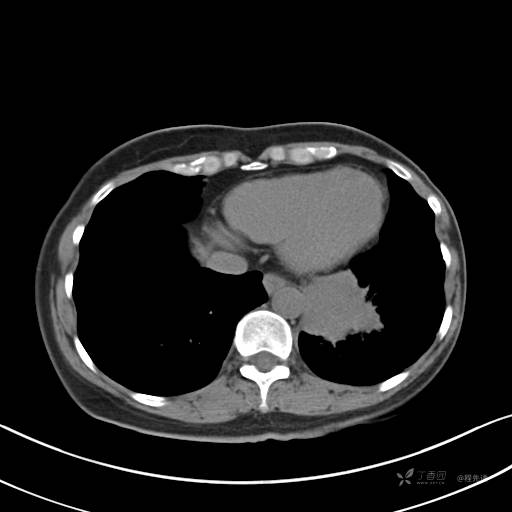

CT平扫

纵隔窗

病灶平扫CT值约31HU